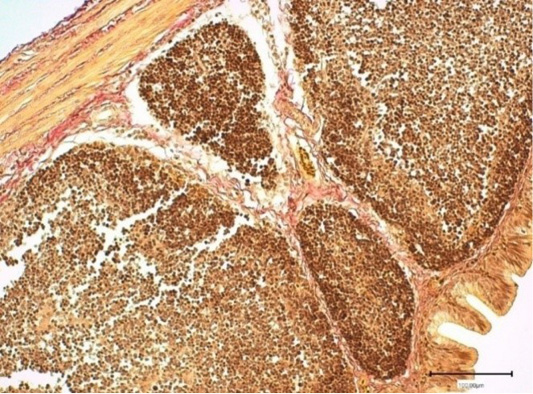

The bursa lobule (lymphoid follicle) of the control broiler chickens. Stained with hematoxylin and eosin.